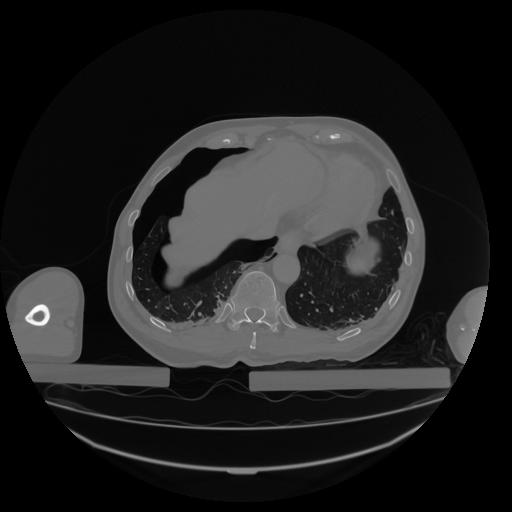

34 CUERPO,CE,Vol,1.0,CUERPO,,